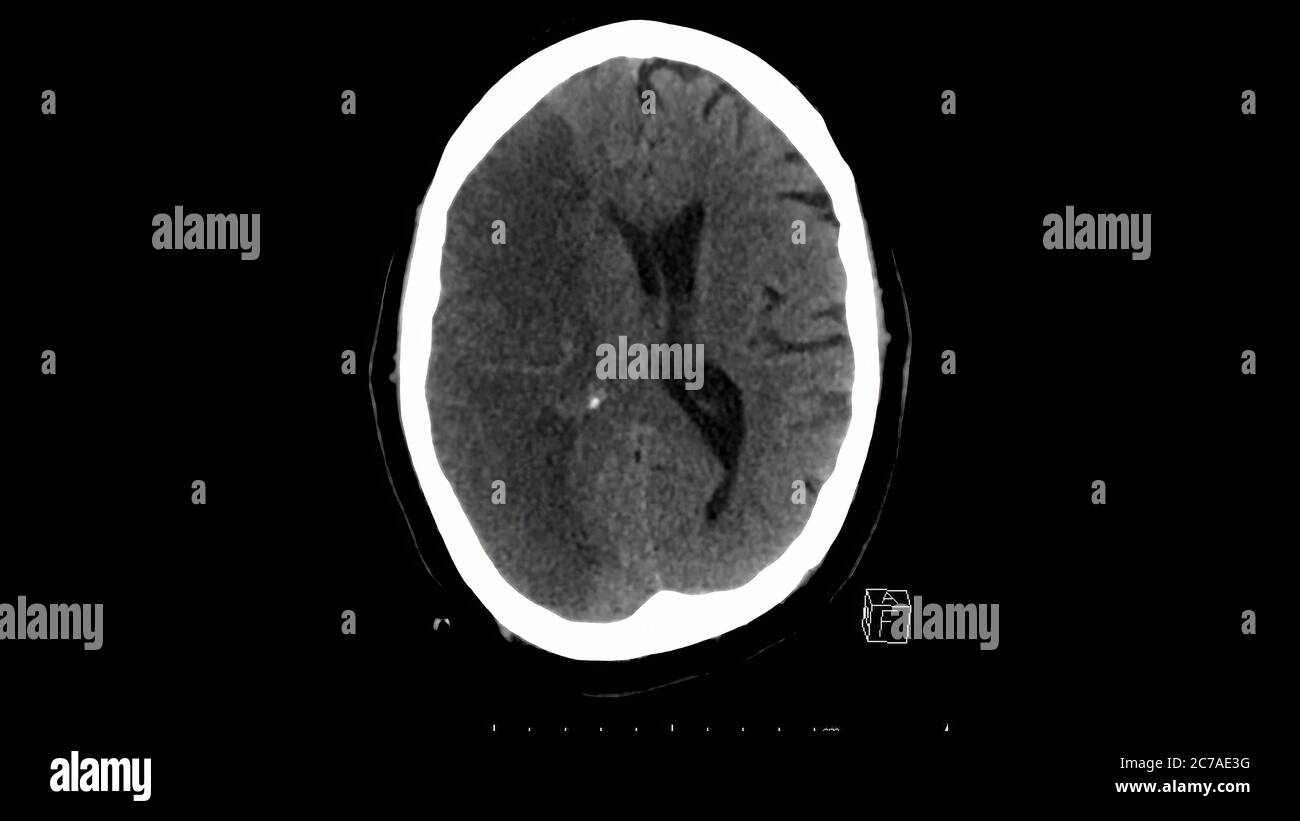

Acquisition tomographique de la coupe axiale du cerveau montrant un infarctus massif de l'artère cérébrale moyenne droite Banque D'Imageshttps://www.alamyimages.fr/image-license-details/?v=1https://www.alamyimages.fr/acquisition-tomographique-de-la-coupe-axiale-du-cerveau-montrant-un-infarctus-massif-de-l-artere-cerebrale-moyenne-droite-image365950916.html

Acquisition tomographique de la coupe axiale du cerveau montrant un infarctus massif de l'artère cérébrale moyenne droite Banque D'Imageshttps://www.alamyimages.fr/image-license-details/?v=1https://www.alamyimages.fr/acquisition-tomographique-de-la-coupe-axiale-du-cerveau-montrant-un-infarctus-massif-de-l-artere-cerebrale-moyenne-droite-image365950916.htmlRF2C7AE3G–Acquisition tomographique de la coupe axiale du cerveau montrant un infarctus massif de l'artère cérébrale moyenne droite